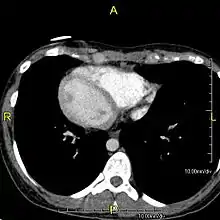

| Situs inversus causes the positions of the heart and lungs to be mirrored. | |

Situs inversus (also called situs transversus or oppositus) is a congenital condition in which the major visceral organs are reversed or mirrored from their normal positions. The normal arrangement of internal organs is known as situs solitus. Although cardiac problems are more common, many people with situs inversus have no medical symptoms or complications resulting from the condition, and until the advent of modern medicine, it was usually undiagnosed.

Situs inversus is found in about 0.01% of the population, or about 1 person in 10,000. In the most common situation, situs inversus totalis, it involves complete transposition (right to left reversal) of all of the viscera. The heart is not in its usual position in the left chest, but is on the right, a condition known as dextrocardia (literally, "right-hearted"). Because the relationship between the organs is not changed, most people with situs inversus have no associated medical symptoms or complications.[1]

The condition affects all major structures within the thorax and abdomen. Generally, the organs are simply transposed through the sagittal plane. The heart is located on the right side of the thorax, the stomach and spleen on the right side of the abdomen and the liver and gall bladder on the left side. The heart's normal right atrium occurs on the left, and the left atrium is on the right. The lung anatomy is reversed and the left lung has three lobes while the right lung has two lobes. The intestines and other internal structures are also reversed from the normal, and the blood vessels, nerves, and lymphatics are also transposed.

If the heart is swapped to the right side of the thorax, it is known as "situs inversus with dextrocardia" or "situs inversus totalis". If the heart remains on the normal left side of the thorax, a much rarer condition (1 in 2,000,000 of the general population), it is known as "situs inversus with levocardia" or "situs inversus incompletus".

Diagnosis of situs inversus can be made using imaging techniques such as x-ray, ultrasound, CT scan, and magnetic resonance imaging (MRI).[7]